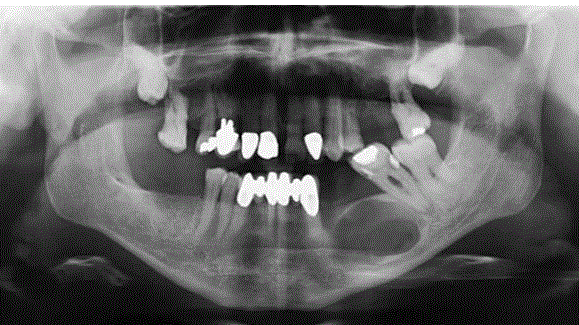

Befunde dieses RÖ-Bild

Panoramaschichtaufnahme. Zystischer Prozess im Unterkiefer links im Bereich der Schaltlücke in regio 36 ohne Lagebeziehung zum Zahnbestand.

Histologie: radikuläre Zyste. Diagnose: Residualzyste [nach Zahn- Extraktion]

Panoramaschichtaufnahme.

Zystischer Prozess im Unterkiefer links mit

Lagebeziehung zum wurzelgefüllten Zahn 37.

Histologie: radikuläre Zyste